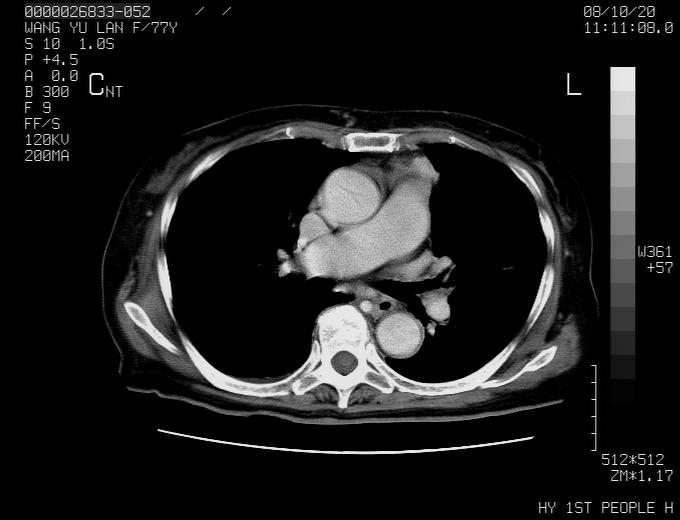

女性,77岁,胸部疼痛半月。左上肺团块影,本人考虑血管畸形,请分析

纵隔有多个淋巴结肿大,提示周围型肺癌并转移可能性大。

动脉期未见大血管同步强化,首先考虑周围型肺癌

动脉期病灶近中线侧可见星芒状与大血管同等强化密度,支持考虑血管畸形伴血栓形成,动脉期不曲型,不除外周围型肺癌

左肺周围型肺癌并肺门淋巴结转移,很典型了!